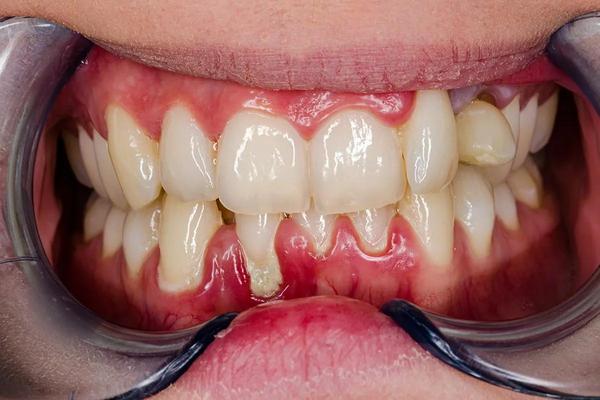

Your dentist may recommend extraction if you have:

• Severe tooth decay beyond repair

• Infection that cannot be treated with root canal

• Broken or fractured tooth

• Impacted wisdom tooth

• Overcrowding before orthodontic treatment

1. Consultation & X-Ray

• Dentist examines the tooth

• X-ray taken to assess roots and bone